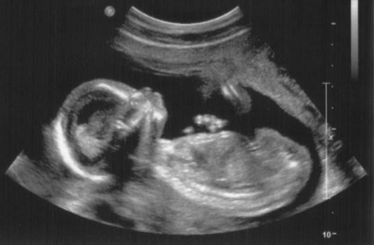

A 23 éves  Annabelle Williams-nek sikerült elkápráztatni az orvosokat, ugyanis 100 millió terhességből csak egyetlen egy ilyen! Szóval nagyon, nagyon ritka dolog történt... A cikk a kép alatt folytatódik!